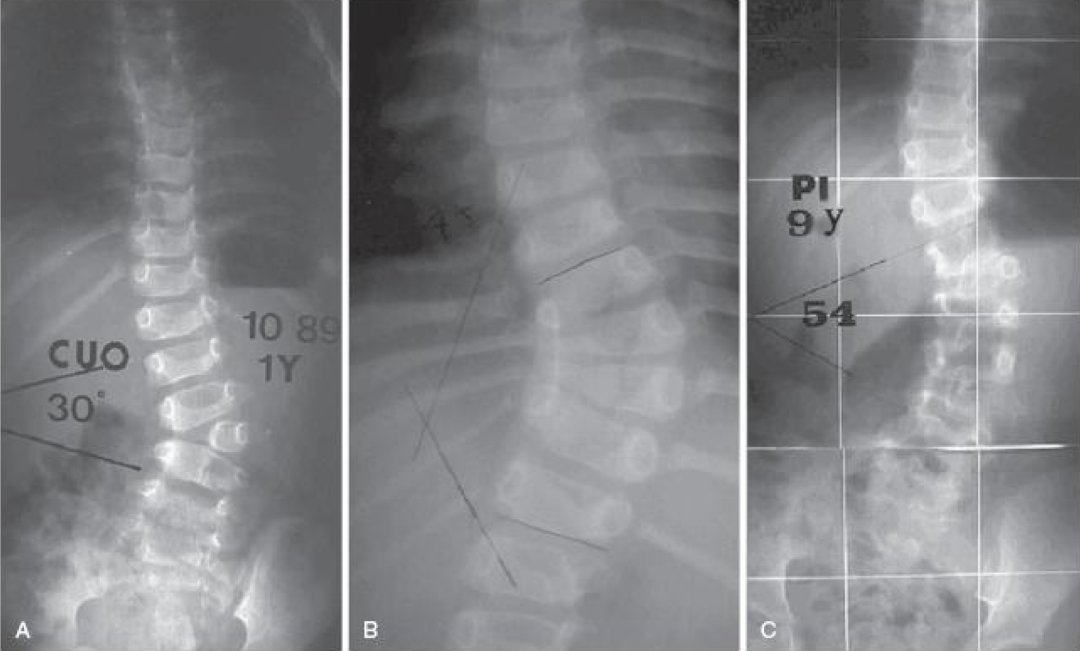

先天性脊柱側(cè)(后)凸

主要考慮對(duì)半椎體進(jìn)行切除,內(nèi)固定矯形融和手術(shù)